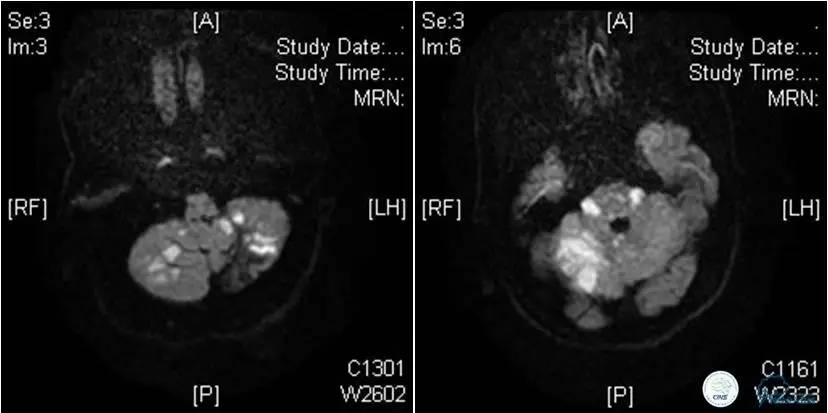

患者:53岁男性,反复脑梗死3个月。

▼给予球囊扩张成形,闭塞段较长,决定药物治疗观察,二期再给予支架治疗。

▼药物治疗1个月,再次发作。再次来我院支架治疗。

▼支架术后,效果好。

因此,某些患者分期治疗也具有合理性。

患者:49岁男性,左侧偏瘫1个月,药物治疗、康复训练效果不好,转我院,肌力0~1级。

core-clilnical明显不匹配,是介入开通的合适患者。